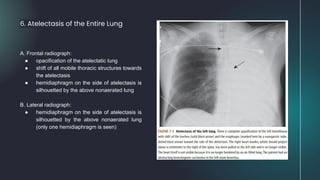

6. Atelectasis of the Entire Lung

A. Frontal radiograph:

● opacification of the atelectatic lung

● shift of all mobile thoracic structures towards

the atelectasis

● hemidiaphragm on the side of atelectasis is

silhouetted by the above nonaerated lung

B. Lateral radiograph:

(only one hemidiaphragm is seen)